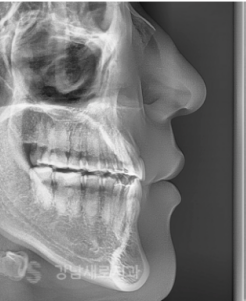

선 수술후 비발치 주걱턱 교정 전/후

또한, 골격의 부조화가 해결된 상태에서

교정 치료를 시작하기 때문에

치아 교정의 결과를 더 정확하게

예측할 수 있어 그만큼 완성도를

높인 치료를 기대할 수 있다고 했어요.

또한 준비 교정이 생략되면서

교정 기간 또한 적어도

6개월 이상 단축할 수 있으며,